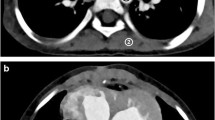

The quantitative analysis of vessel lengths showed that Veo™ images depicted PA, SA and RA vessels of longer lengths than on ASIR™ images (Table 4 and Fig. 2). Furthermore, the number of branch vessels depicted in the apical segment of the right upper lobe PA was consistently greater in number for each subject (Fig. 3) and significantly different on Veo™ (mean number of branch vessels ± standard deviation = 8.7 ± 2.5) vs. ASIR™ (4.3 ± 1.7, P < 0.0003). This better depiction of branch vessels by Veo™ was also well visualized on volume-rendered images (Fig. 4). Vessel tracking also illustrated how Veo™ provided an improved depiction in the terminal vessels with less noise and less variation in luminal size (Fig. 5).

A 7-month-old boy with congenital pulmonary airway malformation. The identical location of a peripheral branch of the right hepatic artery was tracked using thin-slice images obtained from Veo™ (a) and ASIR™ (b) algorithms. The dataset created with Veo™ produces vessel-tracking images with visibly less noise; also, the graph of estimated luminal diameter (shown below each image of the tracked vessel) has considerably less variation with Veo™